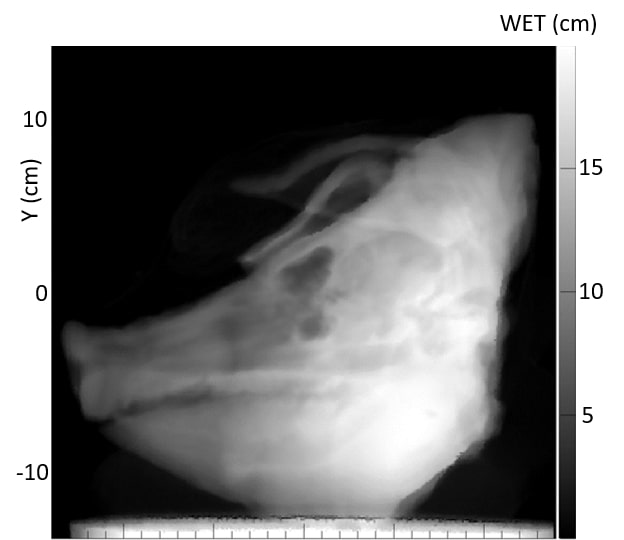

3.B. Comparison of acquired pRad with simulated pRad DRR

Fig. 4 shows the acquired pRad WET image of the pig’s head, along with the simulated pRad DRR from the x-ray CT with the corresponding difference image, and a simulated pRad DRR from the pCT with the corresponding difference image. Relatively large differences around the edges of the head and other areas of rapid variation occur because they are sensitive to a precise alignment of the two images. The four CT markers are visible in the x-ray CT difference image (Figure 4 middle row) at coordinates near (-9,1), (3,0), (3,9), and (11,10) cm. These markers have high x-ray attenuation but do not have a correspondingly high RSP. They are well-aligned in the difference image and appear with net negative WET values since x-ray CT overestimates the RSP of the marker materials. In the case of the pCT difference image (Figure 4 bottom row), the marker RSPs are identical, and therefore the markers are not visible. The slight difference of about 1 mm observed in the air around the pig’s head is likely due to a calibration issue for the 120 MeV protons that travelled deep inside the scintillator. There is a faint grid structure visible in the background of the x-ray CT difference image; this is an artifact due to non-uniformities in the construction of the tracking plane. We are currently upgrading the system, and expect to correct these non-uniformities in the next version.

Most soft-tissue regions of the head, including the brain and head and neck muscles, show agreement within 1-2 mm of WET between the acquired pRad and simulated pRad DRR, 1% in comparison to a total WET of up to 200 mm. The most notable anatomical WET differences are in the sinus region and the tympanic bullae, where the measured WET from the real pRad is 4 to 8 mm lower than the WET from the simulated pRad DRR. The sinus result is similar to that reported for a pig’s head in Deffet et al. 8; however their range-probe image did not contain the tympanic bullae. These large differences do not appear in the simulated DRR from pCT. There are smaller discrepancies in bony regions including the skull and mandible.